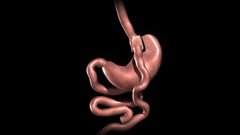

• Laparoscopic Roux-en-Y Gastric Bypass

• Roux-en-Y Gastric Bypass